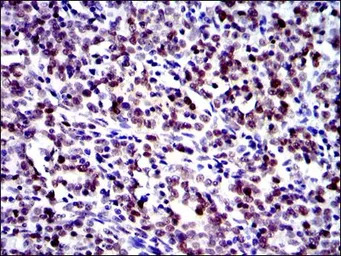

IHC-P analysis of cervical cancer tissue using GTX60485 c-Jun antibody [4H9].

IHC-P analysis of colon cancer tissue using GTX60485 c-Jun antibody [4H9].